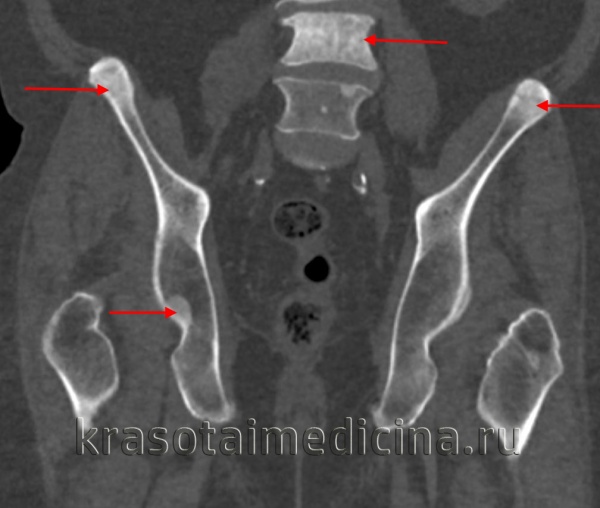

КТ таза. Множественные склеротические очаги в костях таза и позвонках вторичного опухолевого характера.

На рентгеновских снимках выявляется генерализованный остеосклероз. Кости имеют гомогенную структуру, костномозговой канал отсутствует. Метафизы длинных трубчатых костей булавовидно расширены. На рентгенограммах черепа определяется склероз и уменьшение пневматизации синусов. Поздний остеопетроз наследуется по аутосомно-рецессивному типу и проявляется теми же симптомами, однако, заболевание манифестирует в возрасте 10 лет или позже и отличается меньшей распространенностью остеосклероза.